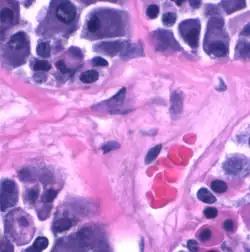

Gonadotrope cellen vertonen basofilie en met hematoxyline-eosinekleuring (H&E) kleuren ze blauwviolet. De gonadotrope cellen lijken afgerond tot veelhoekig en uiteindelijk met lange cytoplasmatische verlengingen. Ze hebben een overvloedig ruw endoplasmatisch reticulum dat hen de karakteristieke kleur geeft en ze hebben ook een overvloed aan celblaasjes en mitochondriën.[10][6]

Op de afbeelding links zijn zichtbaar: De gonadotrope cellen met de kenmerken van polypeptide-uitscheidende cellen. Een ruw endoplasmatisch reticulum met opgezwollen blaasjes. Een groot aantal dichte uitscheidingsblaasjes tussen 300-400 nanometer (nm).[11],[12] De talrijke mitochondriën in het cytoplasma weerspiegelen het hoge energieverbruik.[13] De kernen zijn meestal rond, helder van uiterlijk vanwege het overheersende euchromatine en zijn excentrisch in de cel geplaatst.[14]

De gap junctions zijn zichtbaar, die de communicatie tussen cellen bevorderen en reguleren, waardoor de reacties van de verbonden cellen en daarmee de gonadotrope uitscheidingsfunctie worden gecoördineerd.[15][16]